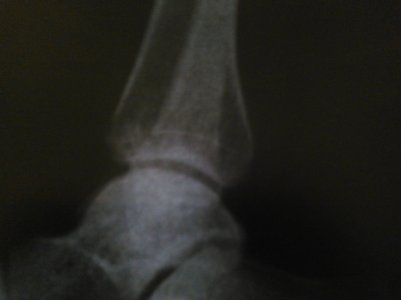

Здравствуйте, мне 39лет. Упала 27ноября2015г. На R- снимке за 27.11.15.и 22.12.15. костных травм, повреждений не выявлено. В лангете проходила 2 недели, 24декабря выписали на работу(на одной ноге прыгала), боль сохранялась в левой стопе, наступать на стопу не могла.

Отдельно прилагаются фото МРТ, КТ, рентгенография.